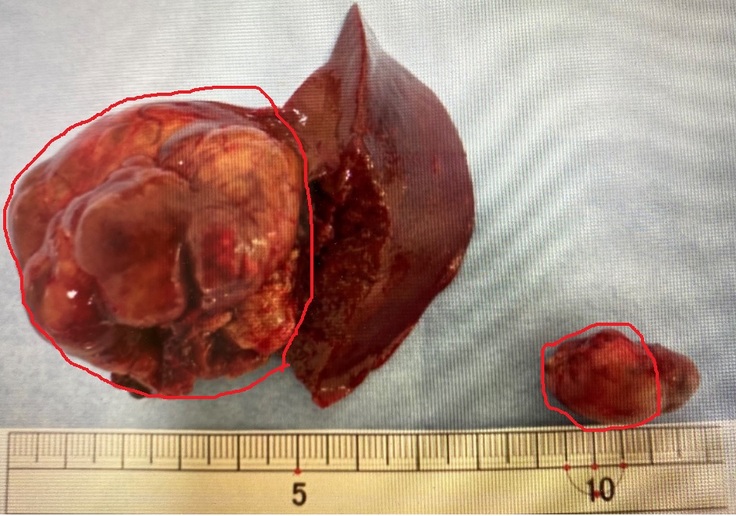

さて、本題の手術で摘出した腫瘍部分は以下の画像は摘出した腫瘍になります。

この角度からだとわかりずらいので別の角度から撮影した画像に赤丸でマークした部分が腫瘍とのことでした。

摘出した腫瘍は生理検査に出して、6月29日に結果がわかりその後の治療方針をどうするか?決めていくそうです。